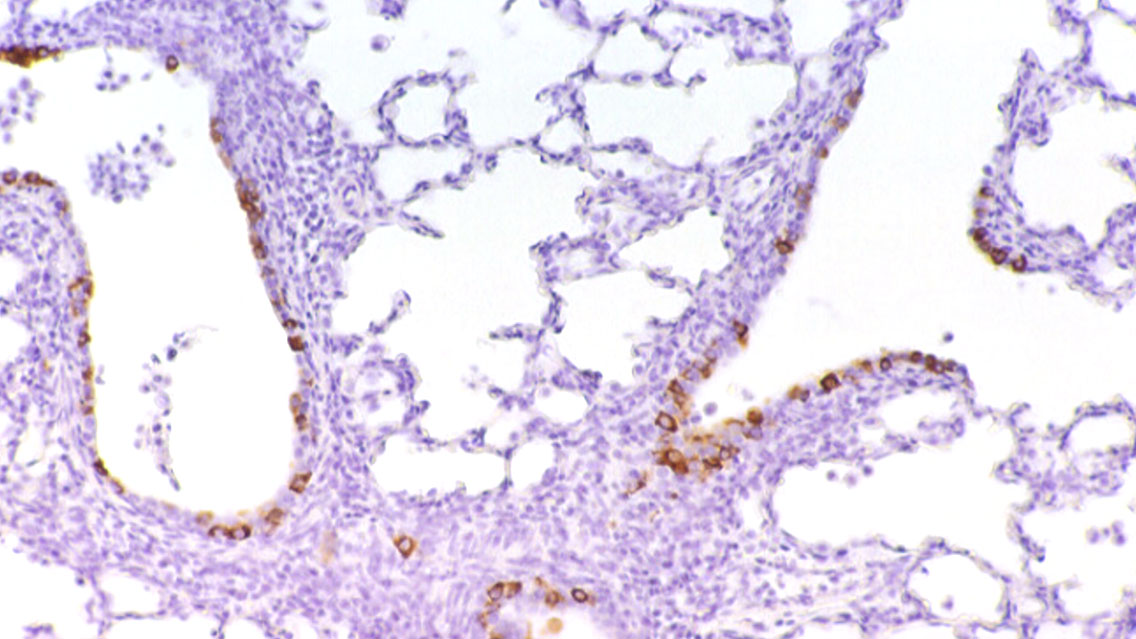

Les lésions pulmonaires causées par le PCV2 sont macro et microscopiquement similaires à celles causées par le SDRPv, car comme celui-ci, il provoque une pneumonie interstitielle et nous devons donc recourir à d'autres techniques de diagnostic telles que l'immunohistochimie (figure 3), l'hybridation in situ ou la PCR afin d'établir le diagnostic. De plus, ce sont deux agents qui sont généralement isolés ensemble car l'infection par le SDRPv est associée à une augmentation de la réplication et de la virulence du PCV2.